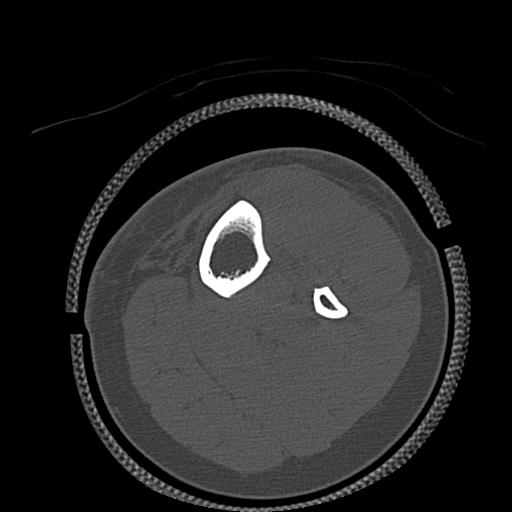

49554 3/13 膝 4R 3/16 4R 1/18 2R 78歳男性 膝蓋骨骨折